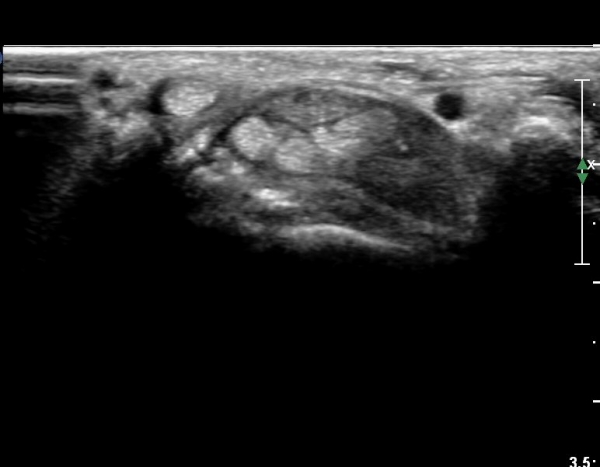

¼ö±Ù°ü Á¾´Ü¸é°Ë»ç¿¡¼ ±¼°î°Ç ½ÉºÎ¿¡ ¼®È¸È¼º À½¿µÀÌ Á¸ÀçÇϰí Àü¹ÝÀûÀÎ ¼öÁö ±¼°î°ÇÀÇ ºñÈÄ, Á¤Á߽ŰæÀÇ ºÎÁ¾°ú

ÈûÁÙ ¹× Á¤Á߽ŰæÀÇ Ç¥ÃþÀ¸·Î ÀüÀ§°¡ °üÂûµÈ´Ù, (»çÁø 5, 6,). ÆÄ¿öµµÇ÷¯°Ë»ç¿¡¼ Ç÷·ùÁõ°¡°¡ °üÂûµÊ´Ù(»çÁø 6).